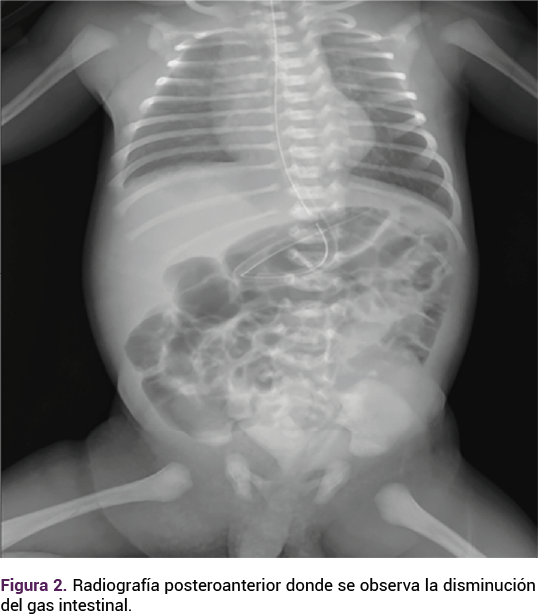

El embarazo finalizó mediante parto espóntaneo con un recién nacido de término, masculino, de 37 semanas por Capurro, placenta y membranas completas, con líquido amniótico de características normales, sin meconio, con talla de 50 cm, peso de 3300 g, Apgar 8-9 con permeabilidad nasal, ano y esófago, a la palpación abdominal con una tumoración de aproximadamente 7 x 5 cm fija, de consistencia dura, peristalsis normal, con el testículo izquierdo en la bolsa escrotal. A la palpación se evidenció la ausencia del testículo derecho en la bolsa escrotal. En la radiografía posteroanterior se observó la disminución del gas intestinal. Figura 3.

<strong>Figura 3</strong>

Figura 3.